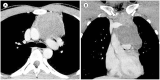

The mediastinum is the most prevalent site of extragonadal teratomas. Patients with mediastinal mature teratomas are usually young adults, and the condition does not show significant sexual differences. Mediastinal teratomas are mostly located in the anterior mediastinum. Patients are usually asymptomatic, although they can have several complications when the teratomas become large or rupture. Most mediastinal teratomas can be diagnosed using CT. Diagnosing ruptured or malignant teratomas is challenging because of their atypical clinical and radiological presentations. In this article, we describe various manifestations of mediastinal teratomas, with an emphasis on radiologic features.